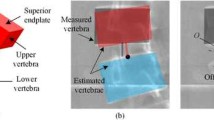

In Petit et al.’s method, the line of action is parallel to the line (iliac line) drawn through the superior tips of the left and right iliac crests in the frontal plane. The force with such a line of action causes the vertebrae to move towards the direction of the bending movement in relation to their inferior vertebrae (Fig. 1). However, in a scoliotic spine, due to the deformity, there is a possibility that a number of the vertebrae move in the opposite direction; an exampleFootnote 2 of a real situation is shared in Fig. 2a. To specify the movement direction of the vertebrae, the relative location of the centreFootnote 3 of the superior (blue, red, and black circles) and inferior (white circles) endplates of the vertebrae is measured on the X-rays of the erect and lateral bending positions (Fig. 2b). The impact of the force (i.e. F and moment τ) with the line of action parallel to the iliac line at the upper centre (black circle) may cause the vertebra to move towards opposite of its actual movement direction. The number of vertebrae with such an opposite movement direction can be large (4 ± 1 out of 14 vertebrae from L4 to T2 [17]), affecting the reconstructed spine shape in the simulated bending.

a Centre of endplates of the vertebrae of a functional spinal unit marked on X-rays of the left bending, erect, and right bending positions of a scoliotic spine and b relative location of the centres and effects of the force to move the centre from its location in the erect position (black circle) to its location in the left/right bending position (blue/red circle) (colour figure online)